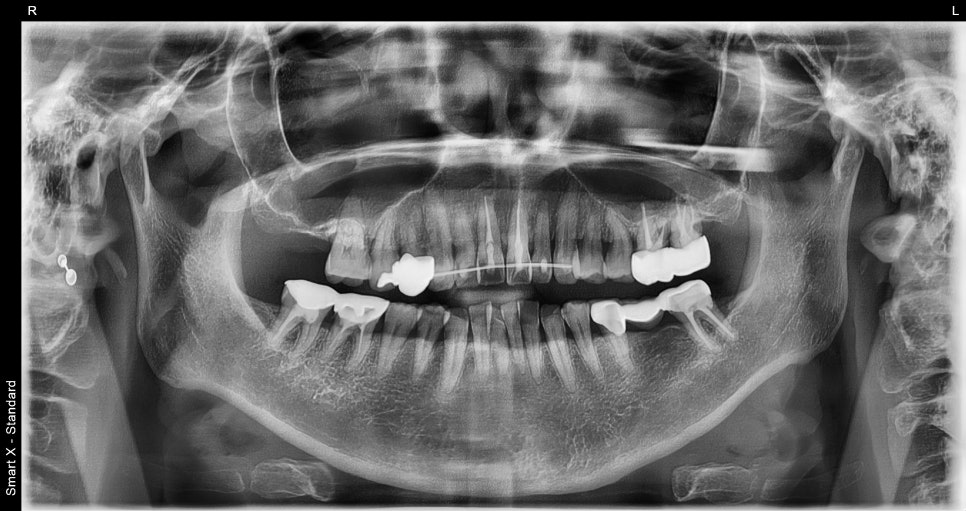

Although it looked like a simple wound, CT imaging revealed

an alveolar bone fracture around the front teeth and tooth displacement.

For this patient as well,

the panoramic X-ray and CT scan clearly confirmed

an alveolar bone fracture around the two front teeth and tooth displacement.

Immediate professional stabilization was needed.